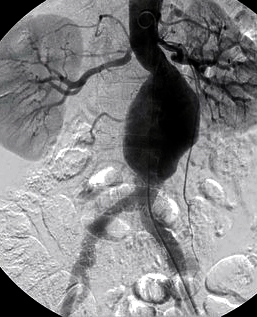

аневризма аорти

Рисунок 2. Комп'ютерна томографія:

1 - зона вільного кровотоку,

2 - тромбована частина аневризми

- ангіографія: дає змогу виявити деформацію аорти та її гілок, однак справжні розміри аневризми не завжди видно у зв'язку з можливою наявністю пристінкового тромбозу порожнини аневризми (рис. 2).

- комп'ютерна томографія (КТ) з контрастним посиленням: дає змогу точно виявити межі та форму аневризми й незмінених відділів аорти, обчислити розміри аорти та прилеглих артерій, оцінити ступінь їхньої звивистості. Одна з найбільш інформативних діагностичних методик, абсолютно необхідна для правильного підбору стент-графту.